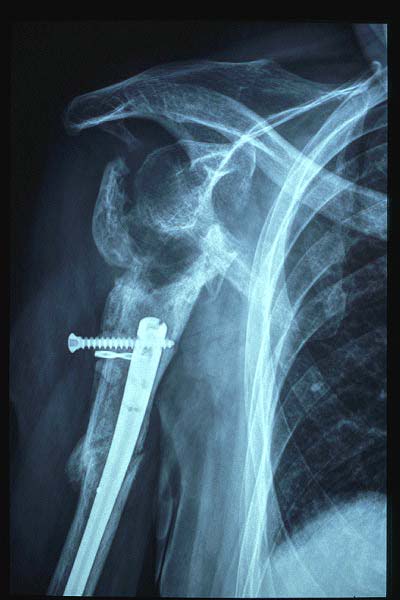

Fractura de húmero, intensa desviación de fragmentos